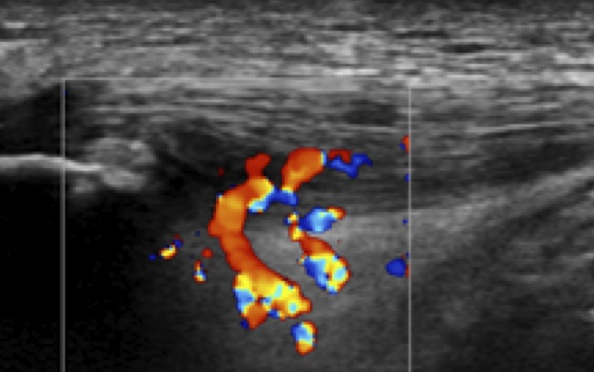

ジャンパー膝の超音波画像(ドプラ)

膝蓋腱近位深層に血流の増加が観察される。